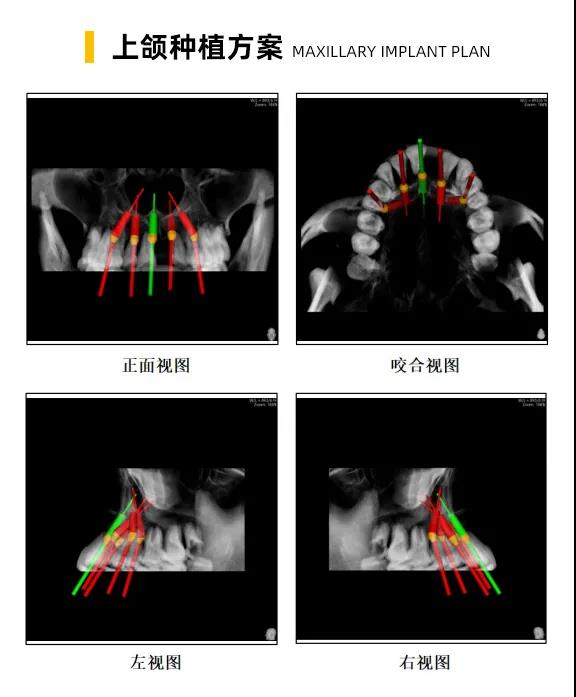

李雪松院长针对她的牙齿情况、牙槽骨的情况设计出一套数字化微创种植方案,拔除口腔余留三度松动牙齿,上下六枚种植体,即刻修复当天就戴上了牙。

数字化种植技术以患者的Sirona CBCT全景影像信息和相关修复信息为基础,借助数字化专业种植设计软件进行术前诊断和种植方案规划;通过数字化种植手术导向模板,将术前制订的种植方案准确应用于种植手术和即刻修复的全过程,实现以修复为导向的牙齿种植修复。

换句话说,运用数字化种植技术就是让所有种植操作可以直观得看到,并且能够看得懂。

它的优势在于种植医生借助数字化设备可以真正实现以修复为导向的种植理念,并且实际运用到临床操作中。